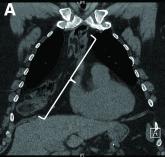

ArticleJanuary 2021 - What's your diagnosis?Author:Alexander Podboy, MDPublish date: December 31, 2020A 68-year-old man presented to our emergency department with sudden-onset melena and associated orthostatic hypotension.Read More